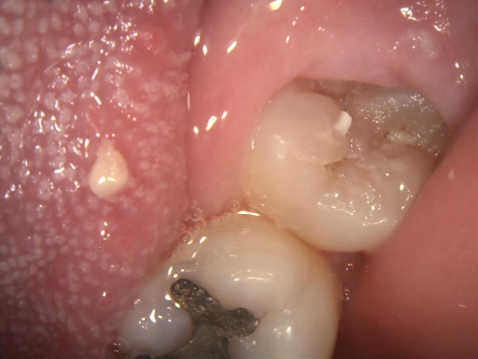

2.親知らずが虫歯になると、その手前の歯も虫歯になる可能性があります

一番右奥の親知らずは良く磨けず、虫歯になることが多いのです。早く抜いて、前の歯が虫歯にならないようにしなければなりません。

同じ症例をレントゲン写真で見たところです。親知らずが横倒しに生えていて、周りの骨を溶かしてしまっています。